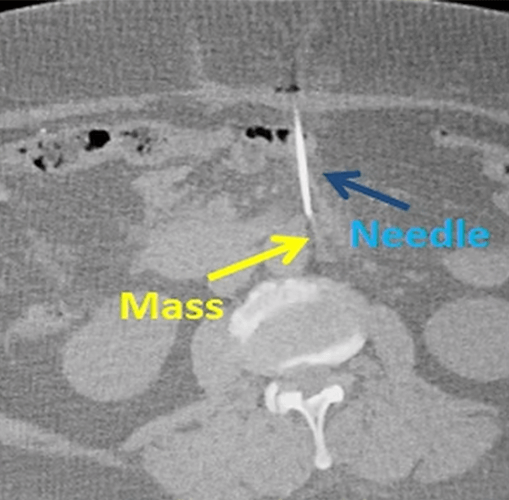

Percutaneous trucut needle biopsy of a 1 cm lymph node adjacent to the aorta under CT guidance.